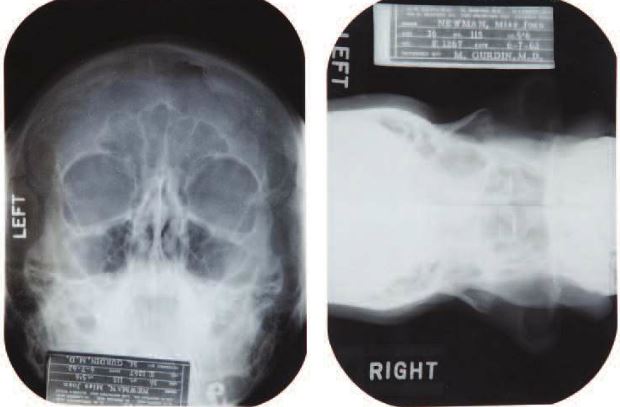

News broke last month that Marilyn Monroe had a little help from plastic surgery to help sculpt that iconically beautiful face of hers, and it was proven via medical records and X-rays that show the work she had done. As of yesterday, those very same records and X-rays sold at an auction in Hollywood for $25,600.

The X-rays and records were part of Julien’s Auctions’ “Icons and Idols: Hollywood” sale, and they cover Monroe’s private medical history from 1950 to 1962. During that time, she had a chin implant to correct what she perceived to be a “chin deformity,” as well as a “tip rhinoplasty” on her nose. A bit more morbidly, the records also detail Monroe’s painful recovery after experiencing an ectopic pregnancy.